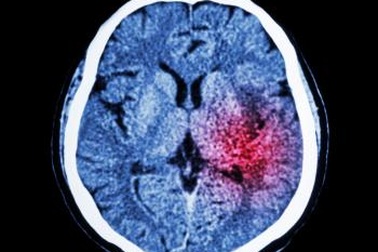

Giao diện não-máy tính cải thiện chức năng vận động cho bệnh nhân đột quỵCác nhà nghiên cứu ĐH Adelaide đã sử dụng giao diện não-máy tính để cải thiện chức năng vận động ở bệnh nhân đột quỵ.

Bệnh nhân đột quỵ đi lại được sau khi ghép tế bào gốcKết quả của một thử nghiệm lâm sàng nhỏ đã mang lại hy vọng cho những người dân bị giảm khả năng vận động sau đột quỵ. Đó là khả năng phục hồi chức năng vận động nhờ tiêm tế bào gốc người lớn vào não đã phục hồi chức năng vận động của bệnh nhân.

Bé trai 3 tuổi bị xuất huyết nội sọ, không nói được do ngạt nướcQua 4 tháng điều trị, một bé trai 3 tuổi ở Bạc Liêu đã hồi phục 70% chức năng vận động do ngạt nước dẫn đến xuất huyết nội sọ, ảnh hưởng não bộ.